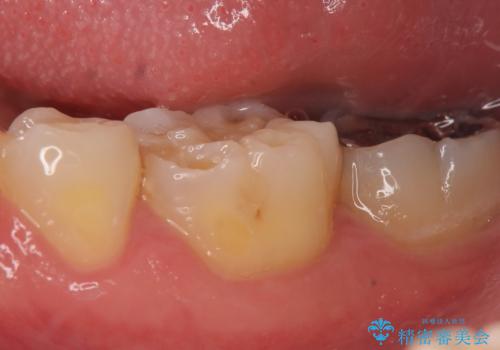

歯が折れた セラミックで綺麗に 30代女性